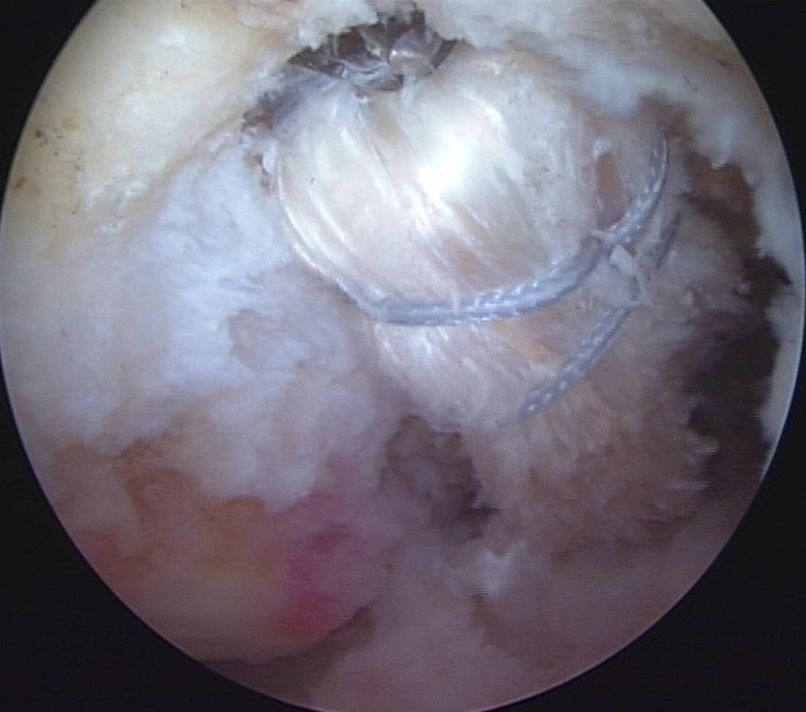

This can be controlled easily under fluoroscopy as the bone block is marked with the 2-hole plate (Fig 24 to 26). The sutures of the bone block are pulled out anteriorly on the tibia and fixed again over a button and in hybrid fixation technique fixed with push lock anchors.

Fig 24 - Arthroscopic  and fluoroscopic control of correct resting position of the bone block in the socket

Fig 25 and 26 - Arthroscopic ( 30° ) and schematic view of the fixed graft